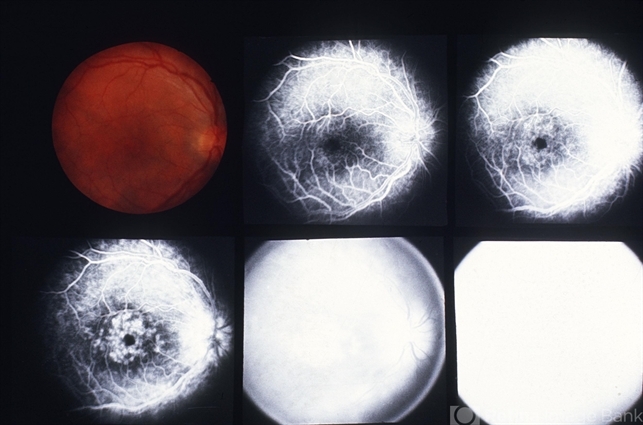

- 80-year-old white female, III IG, right eye: 8/200; left eye: 20/40.